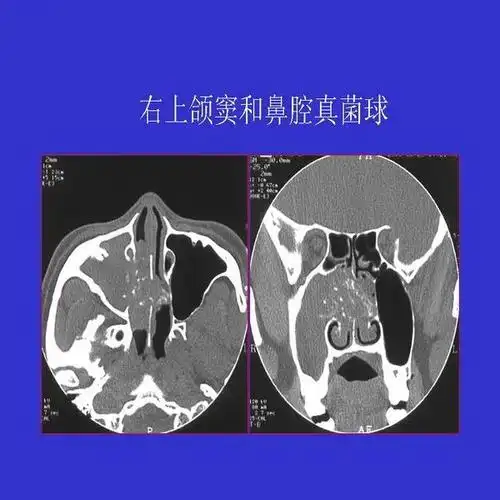

真菌性鼻窦炎影像学诊断